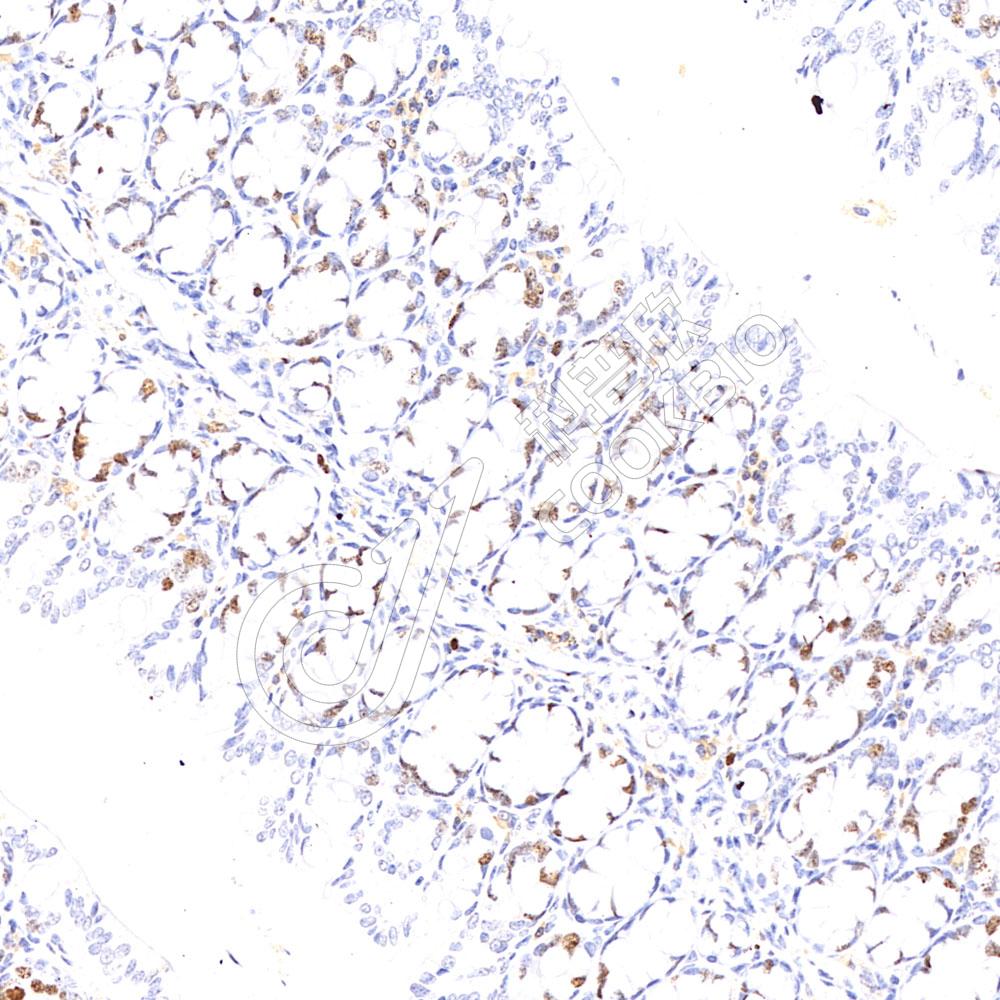

IHC检测Ki67蛋白(货号 K5453423).

样品: 人宫颈癌, 4%多聚甲醛 (货号KSG1101) 固定12-24小时.

抗原修复: 柠檬酸抗原修复液(干粉, pH 6.0) (KSG1201), 高压锅均匀喷气计时2分钟.

—抗: 1: 800稀释, 4℃ 孵育过夜.

二抗: S-vision免疫组化多聚二抗(山羊抗小鼠), 即用型(货号KB3903), 室温孵育20分钟.